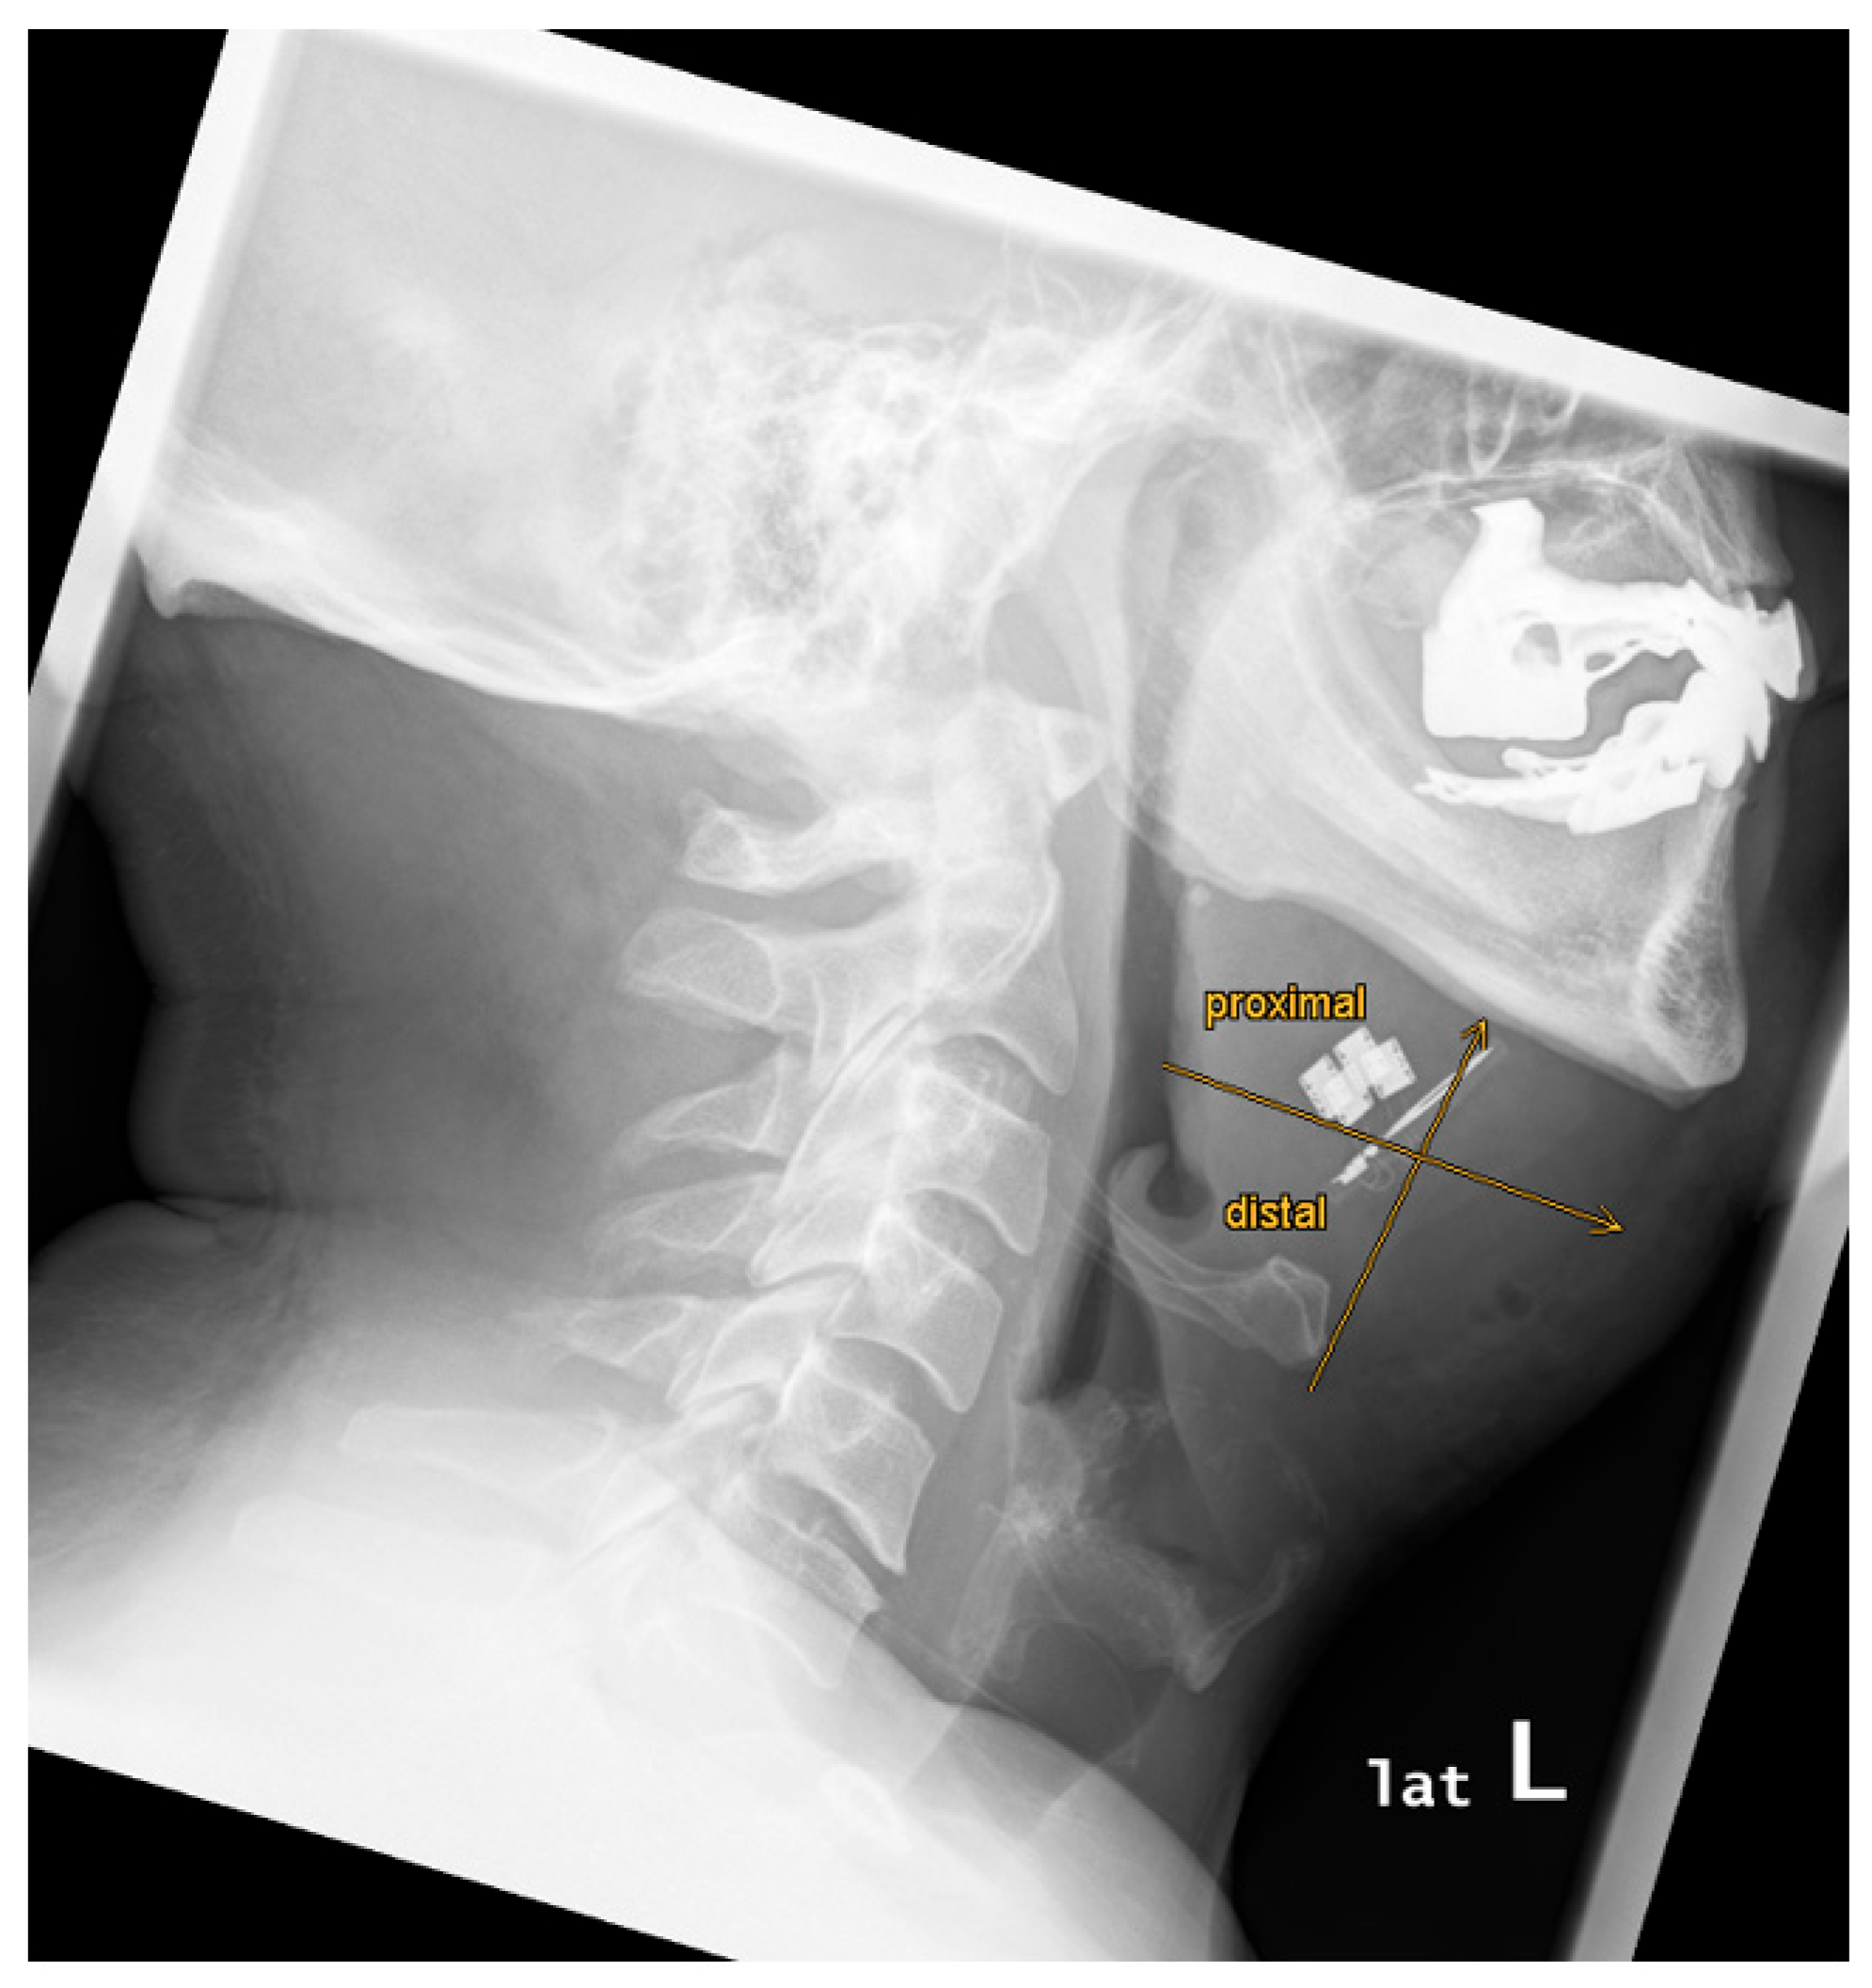

| 1 | 33 | 26 | yes | yes | yes | moderate | no | yes | 87,3 | 28,7 | 56,4 | 15,2 | 7,9 | 22,6 | -14,7 | asymmetry | 64,9 | proximal | proximal |

| 2 | 47 | 30 | yes | yes | yes | strong | no | yes | 94,1 | 45,7 | 57,0 | 19,0 | 18,7 | 19,3 | -0,6 | symmetry | 70,4 | proximal | proximal |

| 3 | 51 | 28 | yes | no | n/a | n/a | no | yes | 109,3 | 32,6 | 48,4 | 17,2 | 15,0 | 19,3 | -4,3 | asymmetry | 60,3 | proximal | proximal |

| 4 | 64 | 31 | yes | yes | yes | moderate | no | yes | 113,9 | 55,3 | 76,2 | 25,9 | 18,8 | 32,9 | -14,1 | asymmetry | 73,8 | proximal | proximal |

| 5 | 37 | 32 | yes | yes | yes | strong | no | yes | 93,2 | 23,9 | 54,5 | 15,4 | 13,9 | 16,9 | -3,0 | asymmetry | 35,3 | proximal | proximal |

| 6 | 52 | 25 | yes | yes | yes | moderate | no | yes | 86,0 | 20,3 | 47,1 | 15,8 | 15,6 | 16,0 | -0,4 | symmetry | 19,0 | proximal | distal |

| 7 | 28 | 28 | yes | yes | yes | moderate | no | yes | 102,0 | 36,7 | 64,3 | 16,4 | 14,4 | 18,3 | -3,8 | asymmetry | 40,7 | proximal | distal |

| 8 | 16,5 | 34 | yes | yes | yes | strong | no | yes | 122,3 | 32,1 | 77,9 | 12,5 | 18,4 | 6,6 | 11,8 | asymmetry | 39,9 | proximal | distal |

| 9 | 32 | 29 | yes | yes | yes | moderate | no | yes | 110,5 | 40,3 | 69,4 | 16,6 | 14,9 | 18,2 | -3,2 | asymmetry | 63,5 | proximal | proximal |